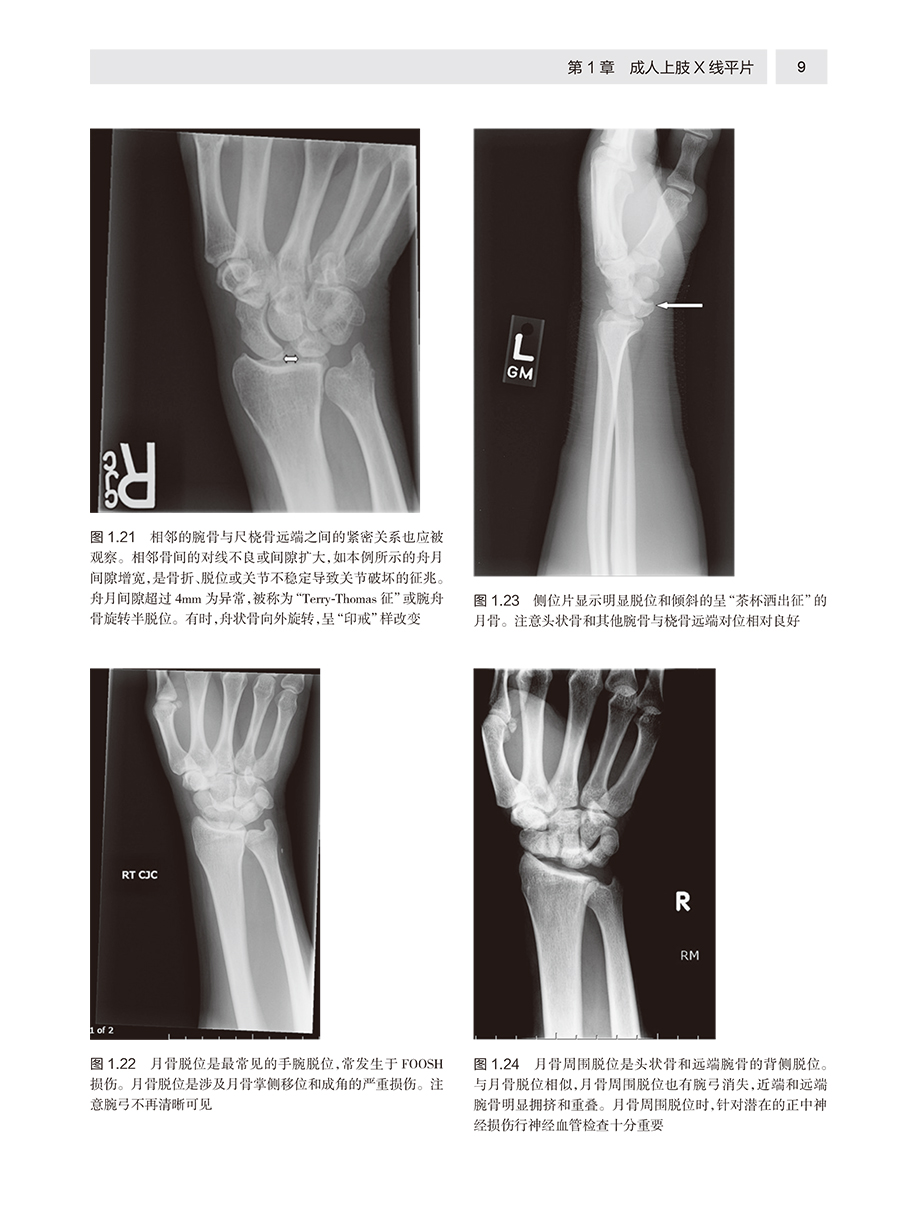

本书分为平片、超声、CT和MRI四部分。每部分依据检查部位组织编写,介绍了急诊影像常见的影像征象基础、影像检查的诊断性、成像陷阱和成像局限性,配有大量真实图像和线条图,内容简明精炼,是院前急救、医院急症室诊治和危重症监护病房等临床领域和急诊影像专业不可多得的资料。 本文介绍了临床急诊放射学的专业知识,包括X线平片、超声、计算机断层扫描、磁共振成像,介绍了各种技术的原理、特征及应用,并配合了大量的临床图片进行说明,给临床工作者提供了很有价值的参考。